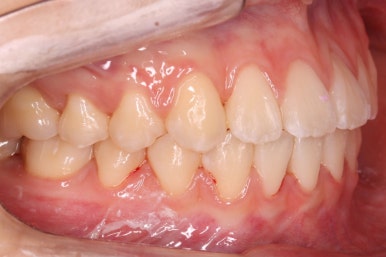

부산교정 키다리아저씨치과에 처음 내원하셨을 때의 입안 모습입니다.

윗니가 삐뚤어져 있고, 아래앞니 사이에는 틈이 듬성듬성 보입니다.

아랫니를 살펴보면 화살표 표시를 해둔 송곳니~송곳니 사이에 치아가 1개 모자랍니다. 원래는 4개의 앞니가 있어야 하는데, 3개 밖에 없었습니다. 이런 결손치아의 경우는 다음과 같은 문제가 생깁니다.